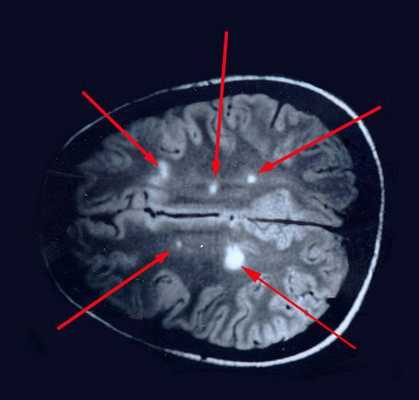

МРТ — магнитно-резонансная томография

На МРТ, в отличие от других лучевых исследований, очень хорошо видно структуру и вещество мозга. Это важно при изучении поражения процессом рассеянного склероза. Современным стандартом является МРТ с контрастом с препаратом гадолиния.

- Локализировать очаги воспаления

- Определить стадию

- Контролировать тяжесть процесса.

Поставить диагноз по данным МРТ в отрыве от клинической картины невозможно, так как изменения в веществе головного мозга не всегда связаны с рассеянным склерозом.

![Очаговые изменения в белом веществе мозга]()

При вероятном РС, наряду с полным неврологическим осмотром, необходимо проводить исследование головного и спинного мозга при помощи МРТ. Этот способ исследования является наиболее информативным дополнительным методом диагностики. С его помощью можно обнаружить участки изменённой плотности в белом веществе головного мозга (очаги демиелинизации и глиоз). [10]

![МРТ мозга]()